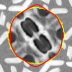

IV-A Tracking Multiple Regions

In cardiac image analysis, there are multiple structures (the right and left ventricles, and myocardium) that all useful and should be segmented. Our method is easily adaptable to this case. Indeed, computation of in Section III-C can be readily generalized. In general, multiple level sets should be used to represent multiple regions. However, in our case of interest (ventricles and surrounding epicardium), the regions form a rather simple topology (see Figure 3), and all regions can be represented using a single level set.